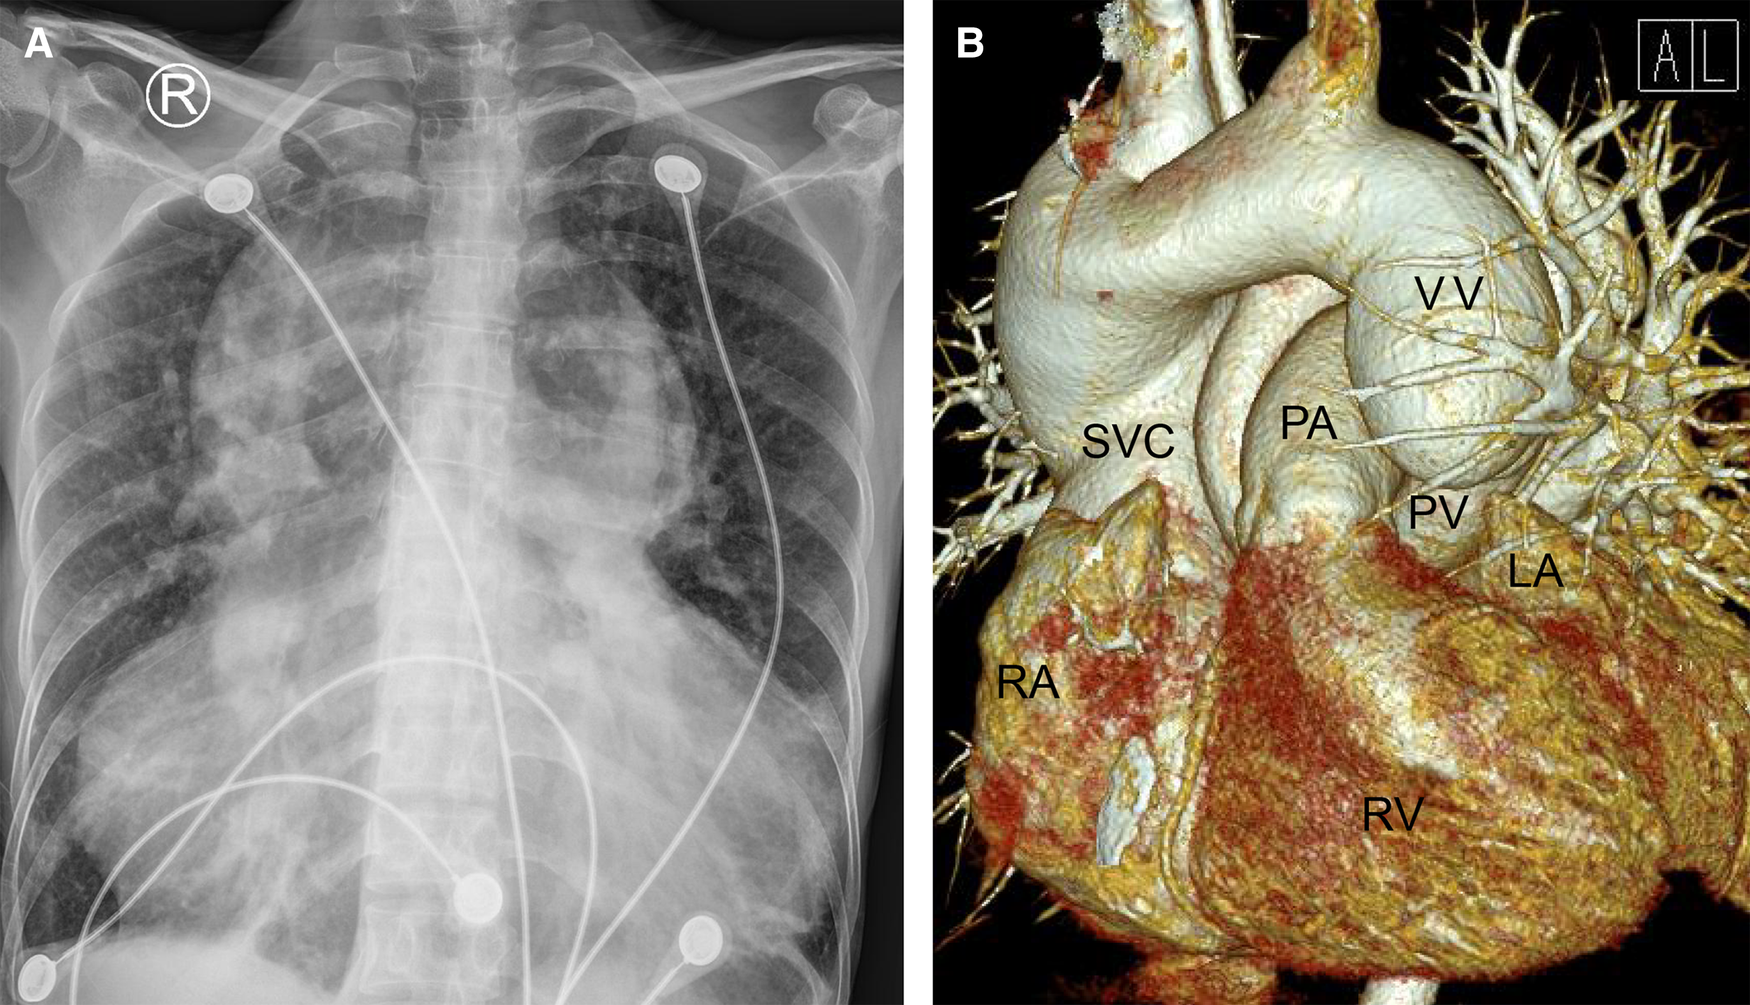

Auscultation revealed a heart rate of 106 bpm, heart sound enhancement, P2 hyperactivity, a right ventriclar outflow tract murmur and a tricuspid diastolic murmur. Physical palpation examination suggested a fluctuated heart apex with a palpable tremor. The routine laboratory examination results were typical except for a high BNP level (1737 pg/ml). Furthermore, the ECG indicated a significant atrial flutter and a right bundle branch block (Supplementary Figure S1A). Preoperative chest radiography indicated that the lungs were textured with a widened mediastinum and a significantly enlarged cardiothoracic ratio of 0.91 (Figure 1A).

Figure 1

Chest radiography (A) and cardiac computered tomograhy angiography (B) preoperatively indicated that the lungs were clearly textured, the heart shadow was significantly enlarged (A); the left and right pulmonary veins were not connected to the left atrium but merged into a vertical vein and drained upward into the left brachiocephalic vein, innominate vein and then the superior vena cava. (B) LA, left atrium; PA, pulmonary artery; PV, pumonary vein; RA, right atrium; RV, right ventricle; SVC, superior vena cava; VV, vertical vein.

On the other hand, a cardiac computer tomography angiography was performed. The three-dimensional reconstruction figure showed that the entire left and right pulmonary veins were not directly drained into the LA but merged into a vertical vein (with a diameter of 44 mm) and flowed upward into the left brachiocephalic vein, IV and then into the SVC (Figure 1B, Supplementary Video S1). Transthoracic echocardiography revealed an atrial septal defect at the lower part of the interatrial septum with right to left shunt and ∼40 mm in diameter (Figures 2A,B). The RA and right ventricle (RV) were enlarged with right ventricular outflow tract hypertrophy. The pulmonary movement was significantly widened, the mean pulmonary arterial pressure was 55 mmHg, and the pulmonary peak velocity was 1 m/s with a pressure gradient and acceleration time of 4mmHg and 50 ms, respectively. The diameter of ascending aorta and the pulmonary trunk were 24 mm and 32 mm, respectively (Figure 2C). The entire four pulmonary veins returned to a vertical vein (around 23 mm), the IV, and the SVC (Figure 2D). Moderate tricuspid regurgitation was also detected. The LA, LV, RA, and RV sizes were 29 mm, 27 mm, 59 mm, and 51 mm, respectively. The LVEDV and LVESV were 28 ml and 10 ml respectively. The EF was 64%, while CO was 2.2 L/min.